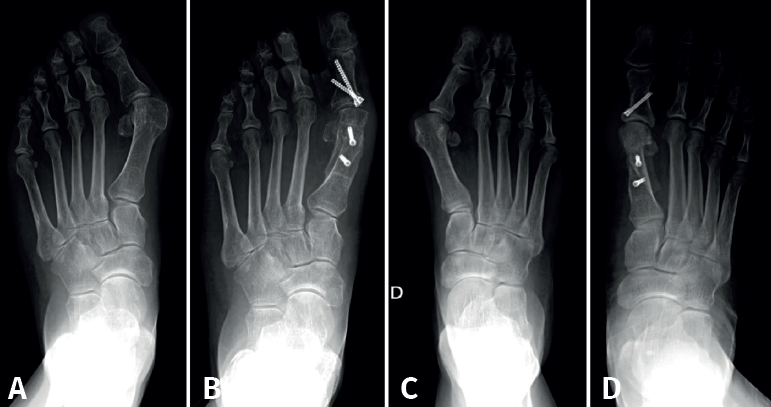

Esta técnica suele ser complementada con una osteotomía de falange proximal del primer dedo (Akin) para corregir la rotación del primer dedo. Algunos ejemplos de pacientes intervenidos en nuestro centro se recogen en la Figura 3.

Figura 3. Ejemplos de hallux valgus intervenidos en nuestro centro: A: pie izquierdo pre-intervención quirúrgica (IQ); B: pie izquierdo post-IQ; C: pie derecho pre-IQ; D: pie derecho post-IQ.